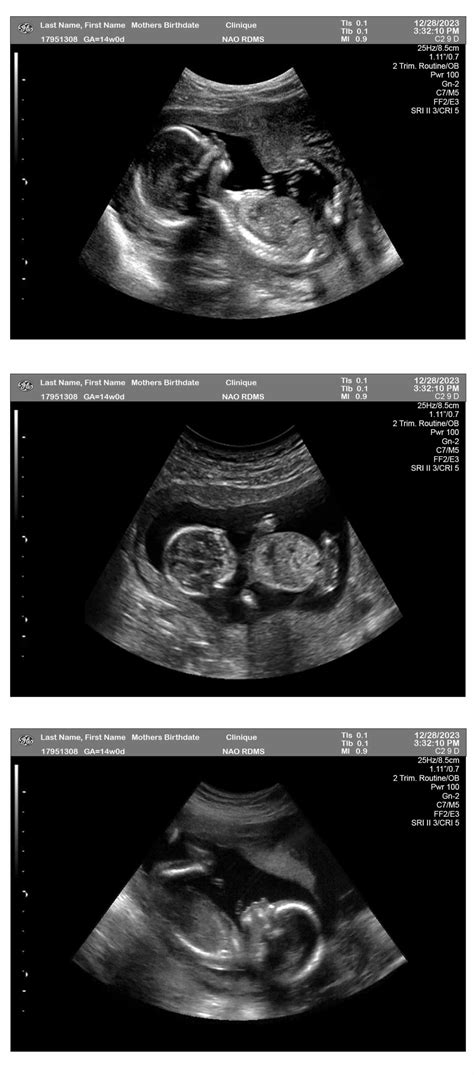

14 Weeks Ultrasound

Pregnancy is an exciting journey filled with milestones, and one of the most anticipated moments is the 14 weeks ultrasound. This scan, typically performed between 13 and 14 weeks of gestation, offers a wealth of information about the developing fetus and the mother's health. Understanding what to expect during this ultrasound can help alleviate anxiety and prepare expectant parents for this crucial check-up.

A 14 weeks ultrasound is a routine prenatal examination that uses high-frequency sound waves to create images of the fetus and the uterus. This scan is usually performed transabdominally, meaning the ultrasound probe is moved over the mother's abdomen. In some cases, a transvaginal ultrasound may be used for a clearer view, especially if the fetus is positioned in a way that makes it difficult to see through the abdomen.

• Confirming the due date by measuring the fetus's crown-rump length (CRL).

• Assessing the fetus's development and checking for any abnormalities.

• Evaluating the placenta and amniotic fluid levels.

• Checking the position of the fetus and the uterus.

• Screening for chromosomal abnormalities, such as Down syndrome, through the nuchal translucency (NT) scan.

The procedure is painless and typically takes about 20-30 minutes. The technician will measure the fetus's CRL, check for the presence of a heartbeat, and assess the overall development. The nuchal translucency measurement, which involves measuring the fluid behind the fetus's neck, is also performed during this scan.

At 14 weeks, the fetus undergoes significant developmental changes. Some of the key milestones include:

• The fetus's head makes up nearly half of its length, and the body is starting to straighten out.

• The fetus's limbs are more proportional, and the fingers and toes are visible.

• The fetus's skin is transparent, allowing the internal organs to be seen.

• The fetus's heart beats strongly, and the blood vessels are visible.

• The fetus's intestines, which had been growing inside the umbilical cord, move into the abdomen.